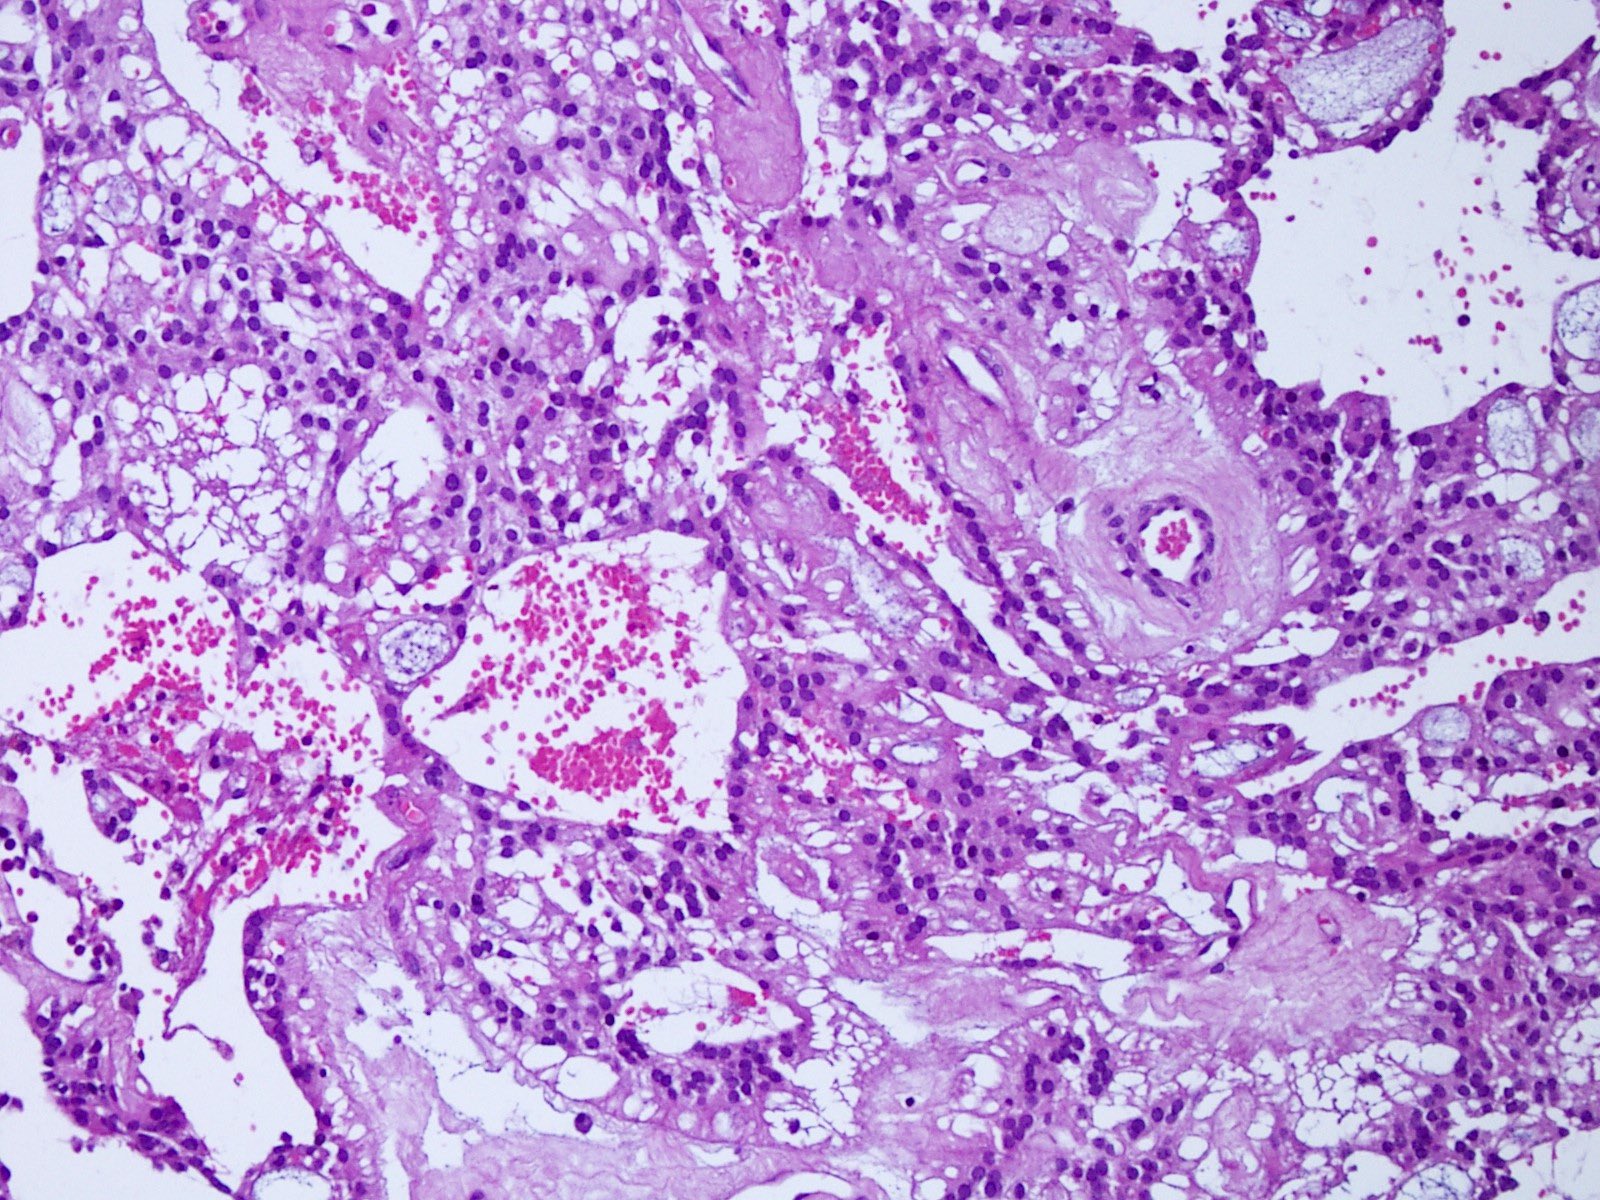

Microscopic (histologic) description

- Most common pattern is radial arrangement of cuboidal to epithelioid elongated glial tumor cells around hyalinized fibrovascular (central, often hyalinized blood vessels) cores in a papillary configuration

- Accumulation of basophilic myxoid material around blood vessels (myxoid stroma) and in microcysts

- Myxoid material is highlighted by PAS and Alcian blue positive staining

- In cases composed of confluent sheets of epithelioid cells with little or no papillary structures, PAS and Alcian blue positivity is useful in reaching a correct diagnosis

- Fascicular growth and spindle cells are common

- Pleomorphic tumor giant cells can be seen

- Occasionally tumor cells show distinctive eosinophilic balloons; these are PAS positive spherules that demonstrate spiculated reticulin staining (Am J Surg Pathol 1996;20:1091)

- Uncommon examples reported as anaplastic myxopapillary ependymomas show hypercellularity and reduced mucin in association with at least 2 of the following features: ≥ 5 mitoses / 10 high power field, Ki67 labeling index ≥ 10%, microvascular proliferation, spontaneous necrosis (Brain Pathol 2019;29:75)

Microscopic (histologic) images